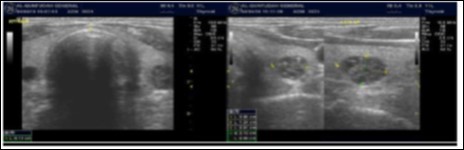

The reported prevalence of nodular thyroid disease depends on the population studied and the methods used to detect nodules 16. Our study population is unique as it is composed entirely of ESKD patients. We also used ultrasound as a method of detecting thyroid abnormalities. In our study the prevalence of thyroid nodular pathology as detected by ultrasound was found to be 57.6% mirror image what reported in the literature as it has been reported that nodules found on ultrasonography suggest a prevalence of 19 to 67%17, 18; and in other publications it has been reported to range from 50% to 70% 7, 8. Figure 3A below shows an Ultrasound detected thyroid nodule.

High-resolution ultrasonography (USG) is the most accurate and cost-effective method for evaluating and observing thyroid nodules 3. Although there is some overlap between ultrasound appearance of benign and malignant nodules, certain USG features are helpful in differentiating the two. Iso-or hyper-echogenicity of the thyroid nodule in conjunction with a spongiform appearance is the most reliable criterion for benignity of the nodule on gray-scale ultrasound, Figure 4A. Other features like nodule size <1 cm, width > length, presence of hypoechoic or hyperoechoic halo around the nodule, Figure 4A and Figure 4B, caused by fibrous capsule compressing thyroid tissue, and coarse/curvilinear calcification are less specific but may be useful ancillary signs4 ,6. "Ring down" or "comet-tail" artifact or sign is typical of benign cystic colloid nodule, Figure 520. Perinodular flow or spoke-and-wheel-like appearance of vessels on color Doppler examination is characteristic of a benign thyroid nodule. However, this flow pattern may also be seen in thyroid malignancy. A complete avascular nodule is very unlikely to be malignant 4.

Figure 4B.Isoechoic nodule with Hyperechoic rim